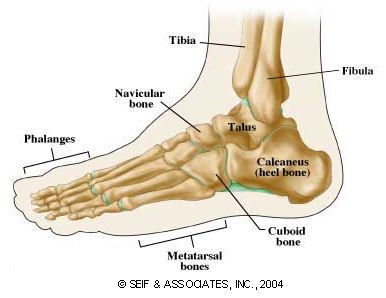

Parts of bone

see attached image